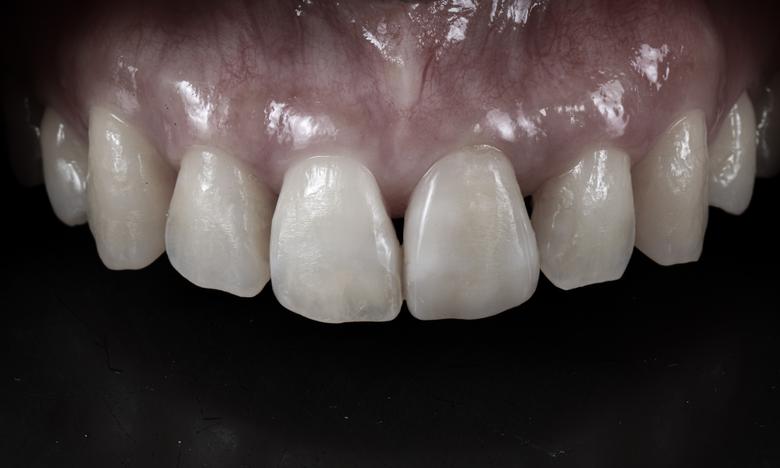

上の前歯6本の中で1本だけインプラントが入っています。どの歯がインプラント=作り物の歯か分かりますか?当院の高度歯科医療ではここまで自然な歯に仕上げることが可能です。